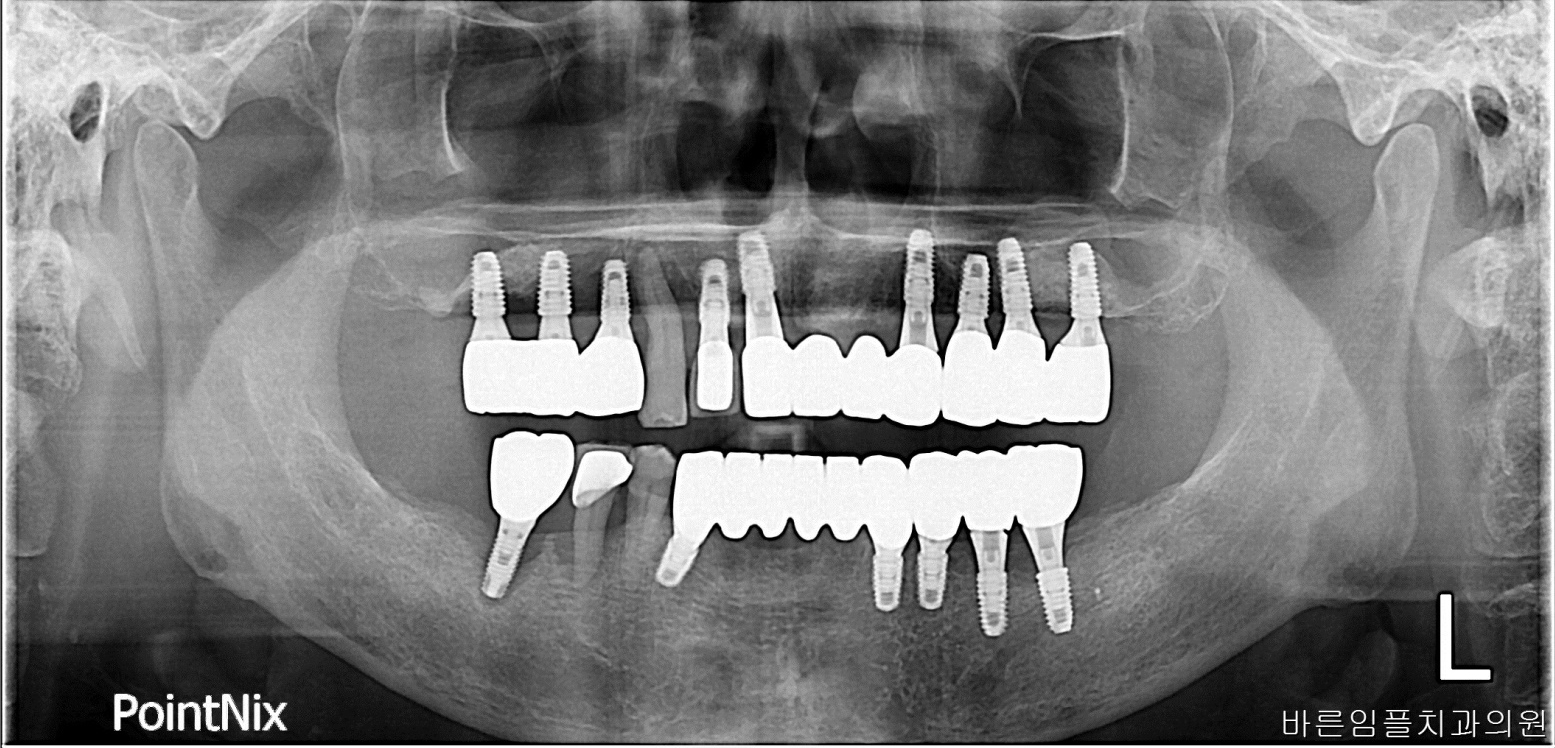

2023-08-03

김ㅇㅇ

After